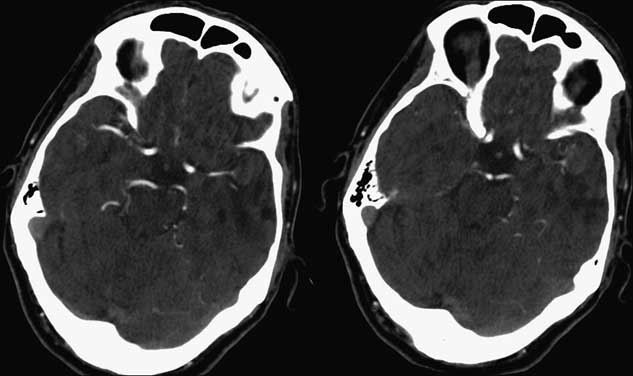

The patient had an uncomplicated hospital stay in the neurosurgical ward, was started on acetylsalicylic acid and clopidogrel, and was eventually transferred to the stroke rehabilitation unit. Prolonged Holter monitor demonstrated no evidence of arrhythmia, an Echocardiogram showed no intracardiac abnormality, and carotid CT Angiogram (CTA) showed no significant stenosis. Follow-up CTA performed 2 and 9 months post-stroke showed no intra-aneurysmal flow and no change in the morphology of the aneurysm dome, wall or thrombus. Partial recanalization of the M1 segment was seen at the MCA bifurcation, though with persistent attenuation of distal MCA branches (Figure 3). Therefore continued surveillance with serial neuroimaging and clinical follow-up is planned.

Figure 3 Follow-up CT Angiogram 11 weeks post-stroke demonstrating unchanged aneurysmal geometry and intensity, with partial recanalization of a distal M2 segment.